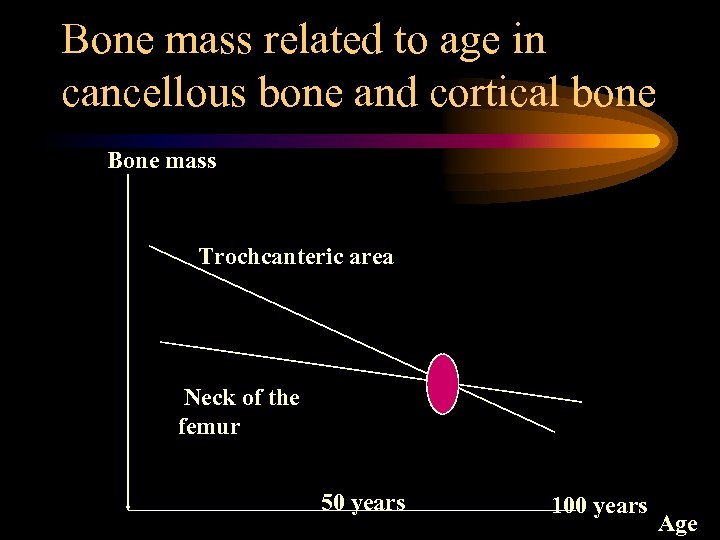

Bone mass related to age in cancellous bone and cortical bone Bone mass Trochcanteric area Neck of the femur 50 years 100 years Age

Bone mass related to age in cancellous bone and cortical bone Bone mass Trochcanteric area Neck of the femur 50 years 100 years Age